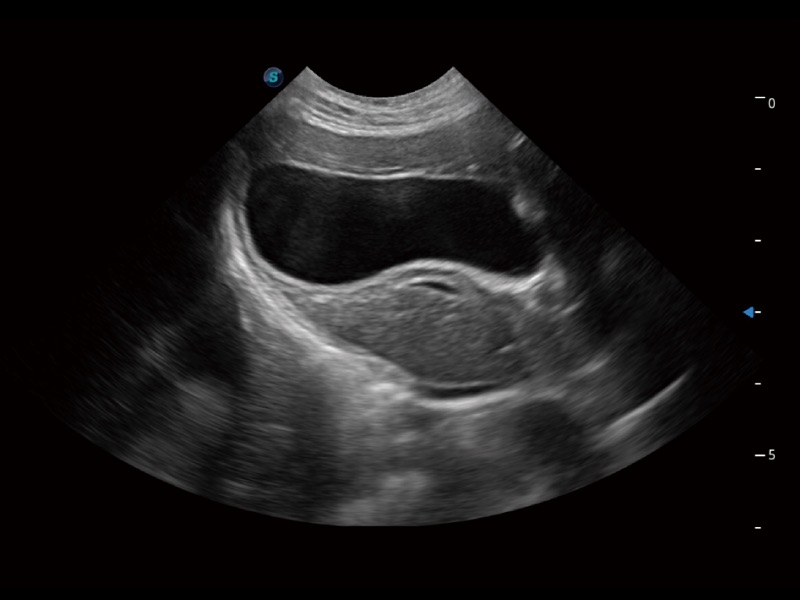

一键自动识别膀胱壁及自动测量膀胱容积,不受膀胱形状和大小的限制,帮助医生快速精准获得测量的数据。

ProPet 70专为动物医生设计,对不同的动物体型和生理结构作出了针对性的优化。通过动物影像专用软件,可满足个性化的应用需求,帮助动物医生获得更精确的诊断数据。